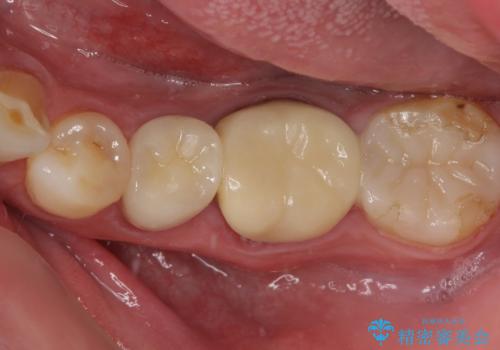

根管治療の際に、咬み合う上顎の銀歯が内側に入り込んでいることも気になるとのことであったため、部分矯正を行い、その後上下を同時に補綴治療することとしました。

部分矯正を行うと咬み合わせが定まらないことがありますが、今回は矯正治療後に上下補綴治療を行ったため、安定した咬み合わせにて仕上げることができました。